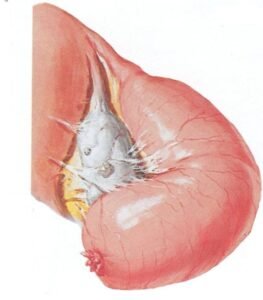

PID can be defined as infection of the upper genital tract involving the cervix (mouth of the uterus), uterus, fallopian tubes, parametria (sides of the uterus and ovaries).